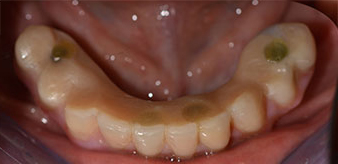

La paciente de 64 años se presentó con una dentición residual compuesta por las piezas dentales 38, 33 y 43 en el maxilar inferior y con una prótesis temporal fijada con ganchos en el maxilar inferior (figs. 1 y 2).

El tratamiento periodóntico necesario y la extracción de las piezas en el maxilar superior debía realizarse en un momento posterior, ya que la paciente es profesora y, en el momento de la consulta, estaba ocupada con los exámenes para las pruebas de acceso a la universidad. La paciente no podía comer ni hablar adecuadamente, ya que la prótesis temporal se rompía con mucha frecuencia y con una carga mínima.

Tras explicarle las distintas opciones de tratamiento, la paciente se decidió por la extracción de la dentición residual en el maxilar inferior, la implantación inmediata y el tratamiento con el método Fast & Fixed (bredent medical), con el que la prótesis dental fijada provisionalmente se atornilla sobre cuatro implantes en el mismo día de la intervención. El objetivo era operar a la paciente el viernes para que el lunes pudiera tomar parte en los exámenes orales para la prueba de acceso a la universidad.